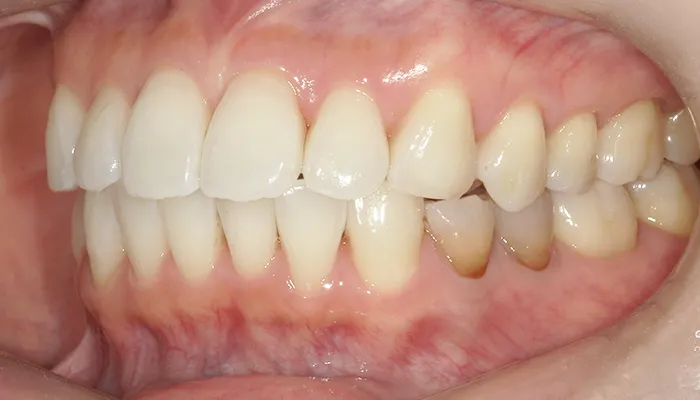

治療後

治療終了後の完成した口腔内と

レントゲン写真

右下5番のインプラントは良好に骨結合し、自然な形態と色調の補綴物を装着しました。

インビザライン矯正により歯列が整い、清掃性・咬合バランスともに改善しました。

ホワイトニングにより歯全体の色調が明るくなり、笑顔の印象が大きく改善しました。

患者様は審美性・機能性ともに大変満足していらっしゃいました。